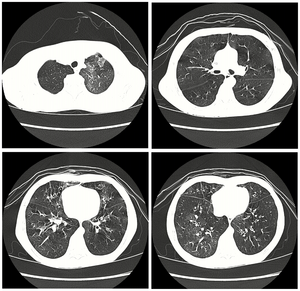

Medical imaging

Early in the disease chest radiography is typically normal but may show hyperinflation.[6] As the disease progresses a reticular pattern with thickening of airway walls may be present.[4][6] HRCT can also show air trapping when the person being scanned breathes out completely; it can also show thickening in the airway and haziness in the lungs.[11] A common finding on HRCT is patchy areas of decreased lung density, signifying reduced vascular caliber and air trapping.[6] This pattern is often described as a "mosaic pattern", and may indicate obliterative bronchiolitis.[6]